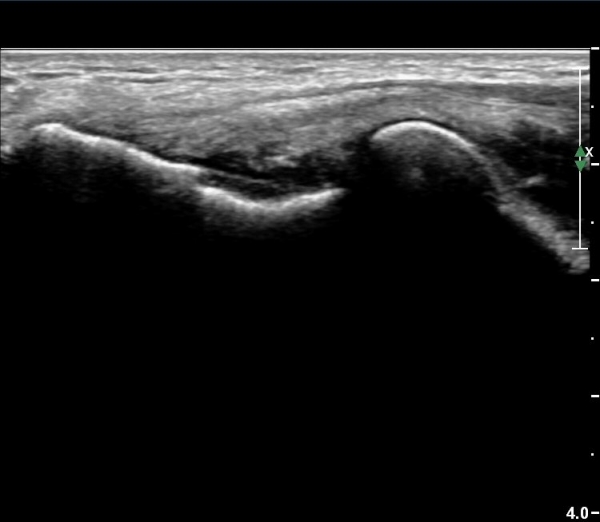

ÃÊÀ½ÆÄ °Ë»ç

ÆÈ²ÞÄ¡ ¾ÕÂÊ ¼ÒµÎ Á¾´Ü¸é°Ë»ç¿Í Ⱦ´Ü